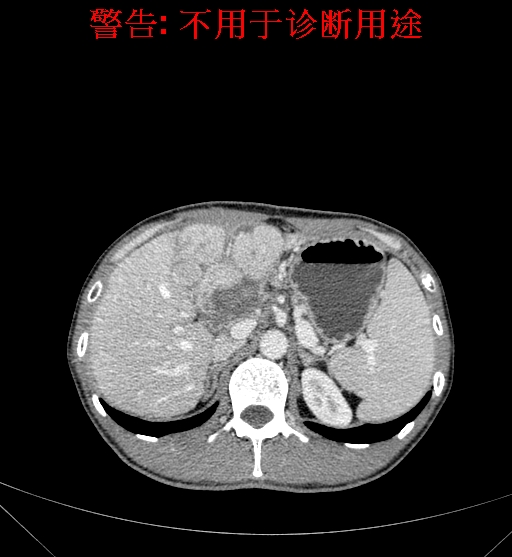

上腹部CT动态增强扫描示肝左叶多发占位性病变,考虑肿瘤,建议MR平扫+增强进一步检查。上腹部MR动态增强示肝左叶肝Ca挤压肝门区结构可能性大,请结合临床综合评价。

术前CT检查:

静脉期